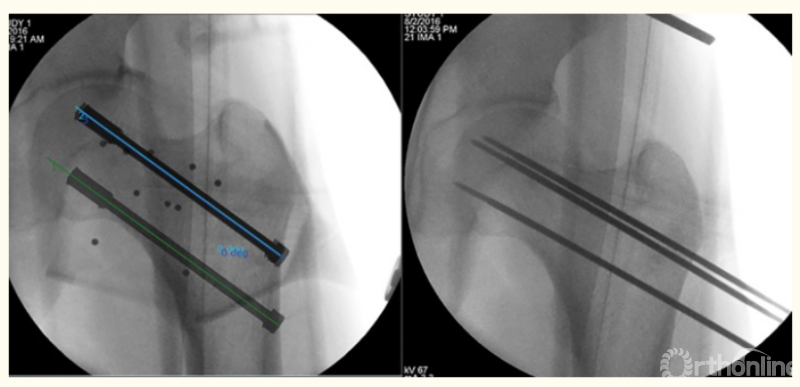

1、肘关节旋转轴三维定位

国内蒋协远教授团队在世界上率先采用三维导航机器人进行肘关节旋转中心定位。TiRobot机器人导航辅助肘关节旋转中心轴定位能够极大地降低主观判断造成的旋转轴偏移,提高轴心定位精准度,减少反复透视验证的过度辐射及反复调整轴心导针的骨质破坏,避免可能的血管、神经损伤,显著减小降低术后肘关节活动阻力,并减少外固定针松动、断裂及外固定架断裂等并发症的发生率,从而整体提高治疗效果。